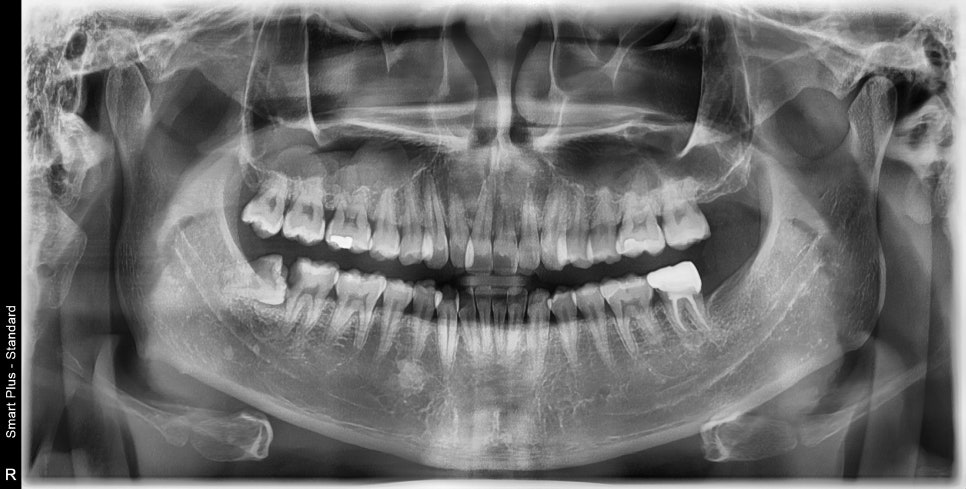

환자분께서 오른쪽 아래 끝 치아가 섞어서 깨진 것 같다고 사랑니 때문인지 궁금해하셔서 내원해 주셨습니다.

하악 우측 매복 사랑니로 인해 앞 치아에 충치가 진행이 많이 되어있는 상태였습니다.

매복 사랑니가 잇몸 밖으로 부분 맹출이 되어있는 경우는 관리가 쉽지 않습니다.

그 앞 치아 사이에 음식물이 껴서 제거가 잘되지 않고, 충치가 생기게 됩니다.

일단 매복 사랑니 발치가 필요하고, 그 앞 치아는 충치의 범위가 잇몸 하방, 신경까지 진행이 되어있는 상태였기 때문에 신경치료를 같이 진행하였습니다.